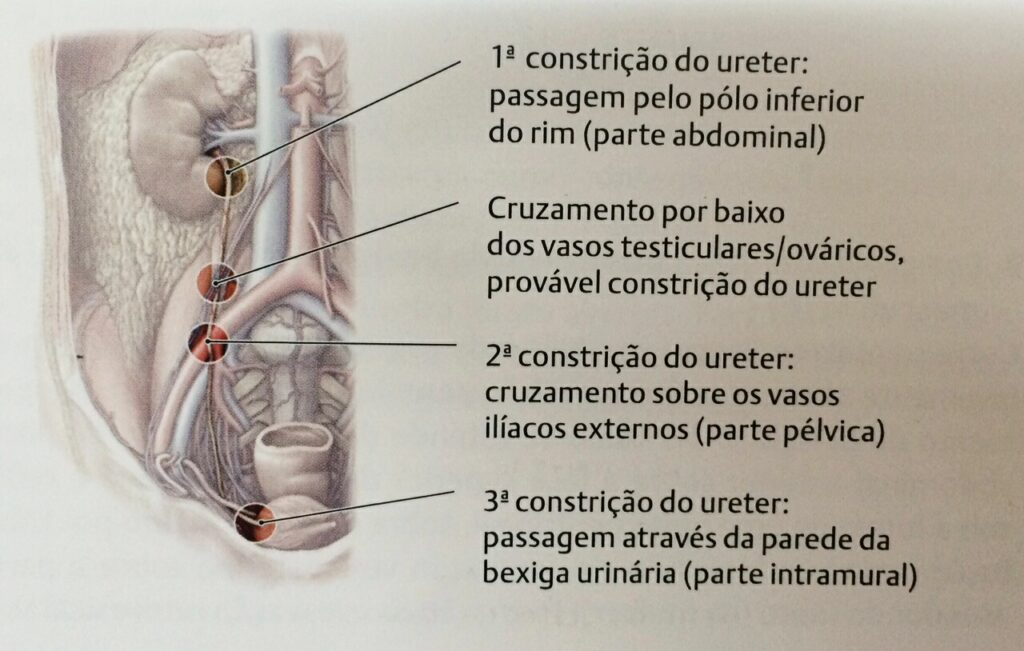

Ureter e sua importância

O ureter é um tubo com cerca de 26 a 29 cm de comprimento no homem adulto, sendo 1 cm mais curto na mulher. Faz parte das vias urinárias ligando a pelve renal até a bexiga. Tem a função de impulsionar a urina até a bexiga através de contrações, mecanismo chamado peristalse (essas contrações são […]